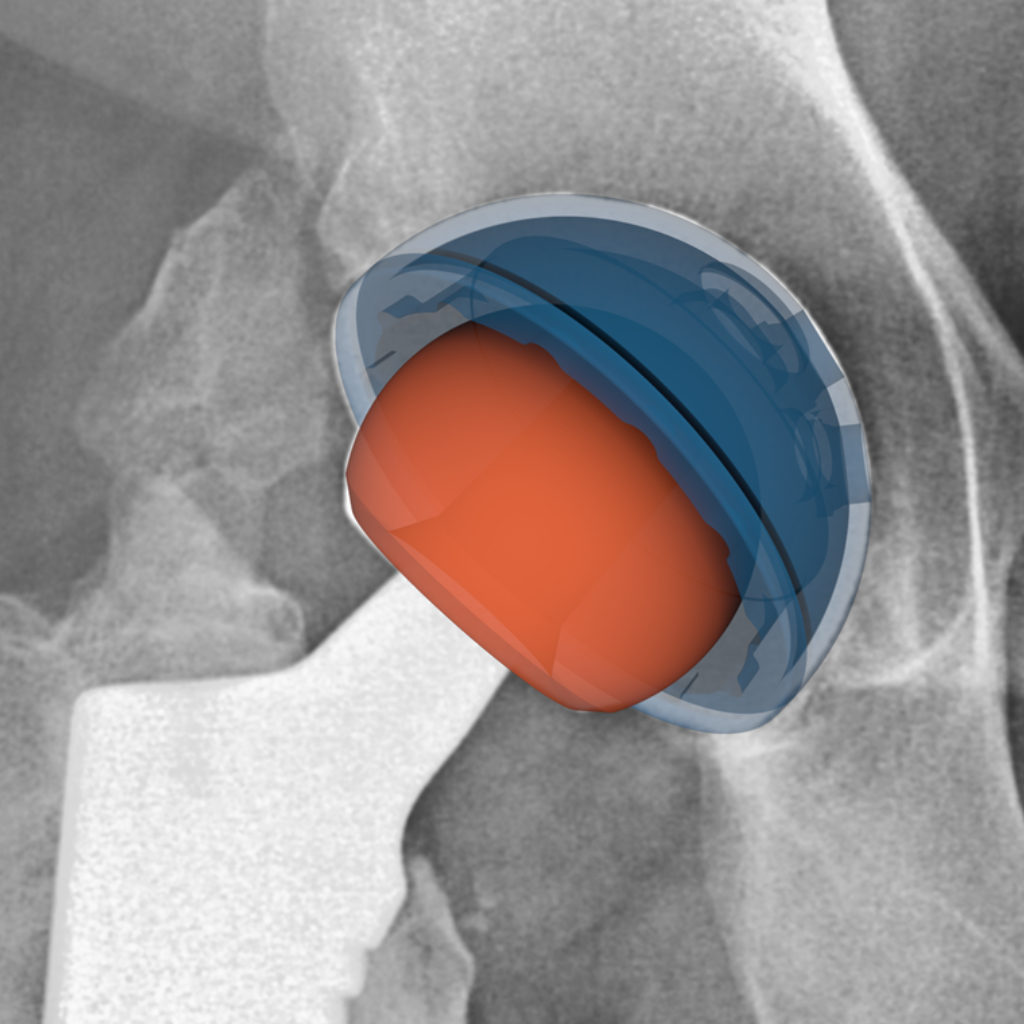

Hip implant component positioning and performance analysis.

We have extensive experience supporting total hip arthroplasty (THA) device manufacturers with radiographic analysis throughout product development—from primary THA through revision procedures and across post-market surveillance.

Our team has developed and validated proprietary 2D-3D image registration techniques that extract precise implant positioning metrics (acetabular cup inclination and anteversion) and linear wear measurements from standard clinical radiographs. This methodology has been applied across multiple clinical studies supporting regulatory submissions, enabling device safety and effectiveness assessments without specialized imaging protocols.

Our THA expertise spans:

- Primary and revision arthroplasty procedures

- Component positioning analysis for conventional and robotic-assisted surgeries

- Long-term migration assessment (femoral stem subsidence, acetabular cup migration)

- Polyethylene liner wear quantification

- Osseointegration evaluation of acetabular components

- Device integrity monitoring and radiolucency detection

We’ve supported THA device manufacturers in generating robust, regulatory-grade evidence across diverse implant designs, bearing surfaces, and surgical approaches.

Cup Inclination and Anteversion

Cup incliniation refers to the angle in degrees (°) of the cup surface against the horizontal (medio-lateral) axis.

Cup anteversion is the angle in degrees (°) of the cup surface against the cup symmetry axis in the frontal plane.

To assess these parameters, CAD models of the implants are required.